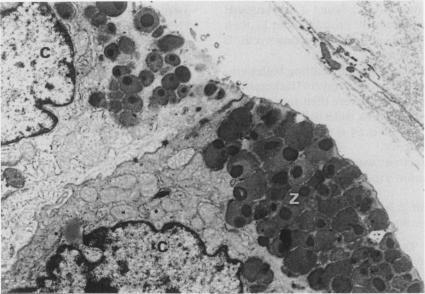

Prostaglandin E1 elevated pepsin activity in gastric mucosa but lowered pepsin activity in the gastric juice of rats treated by pylorus ligation and intragastric administration of hydrochloric acid. In these animals zymogen granules with low electron density were numerous in the gastric chief cells following prostaglandin E1 treatment. The prostaglandin E1-induced increase in mucosal pepsin activity was slightly inhibited by actinomycin D and there was no apparent increase in 3H-thymidine incorporation into gastric mucosa following treatment with prostaglandin E1. It is suggested that prostaglandin E1 causes an elevation of pepsin activity in the gastric mucosa by stimulating pepsin synthesis and perhaps also by facilitating pepsin release from zymogen granules. However, it also appears to inhibit pepsin release from the mucosa into the gastric cavity judging by the decrease of pepsin activity in gastric juice. The reduced pepsin activity in gastric juice may account, in part, for the reported anti-ulcerative action of prostaglandin.

前列腺素E1可提高胃黏膜中的胃蛋白酶活性,但在幽门结扎并胃内给予盐酸处理的大鼠胃液中,却会降低胃蛋白酶活性。在这些动物中,经前列腺素E1处理后,胃主细胞内低电子密度的酶原颗粒数量众多。放线菌素D对前列腺素E1诱导的胃黏膜胃蛋白酶活性增加有轻微抑制作用,且用前列腺素E1处理后,胃黏膜中3H-胸腺嘧啶核苷掺入量无明显增加。提示前列腺素E1通过刺激胃蛋白酶合成,或许还通过促进胃蛋白酶从酶原颗粒中释放,从而使胃黏膜中胃蛋白酶活性升高。然而,从胃液中胃蛋白酶活性降低来看,它似乎也抑制了胃蛋白酶从黏膜向胃腔的释放。胃液中胃蛋白酶活性降低可能部分解释了前列腺素所报道的抗溃疡作用。